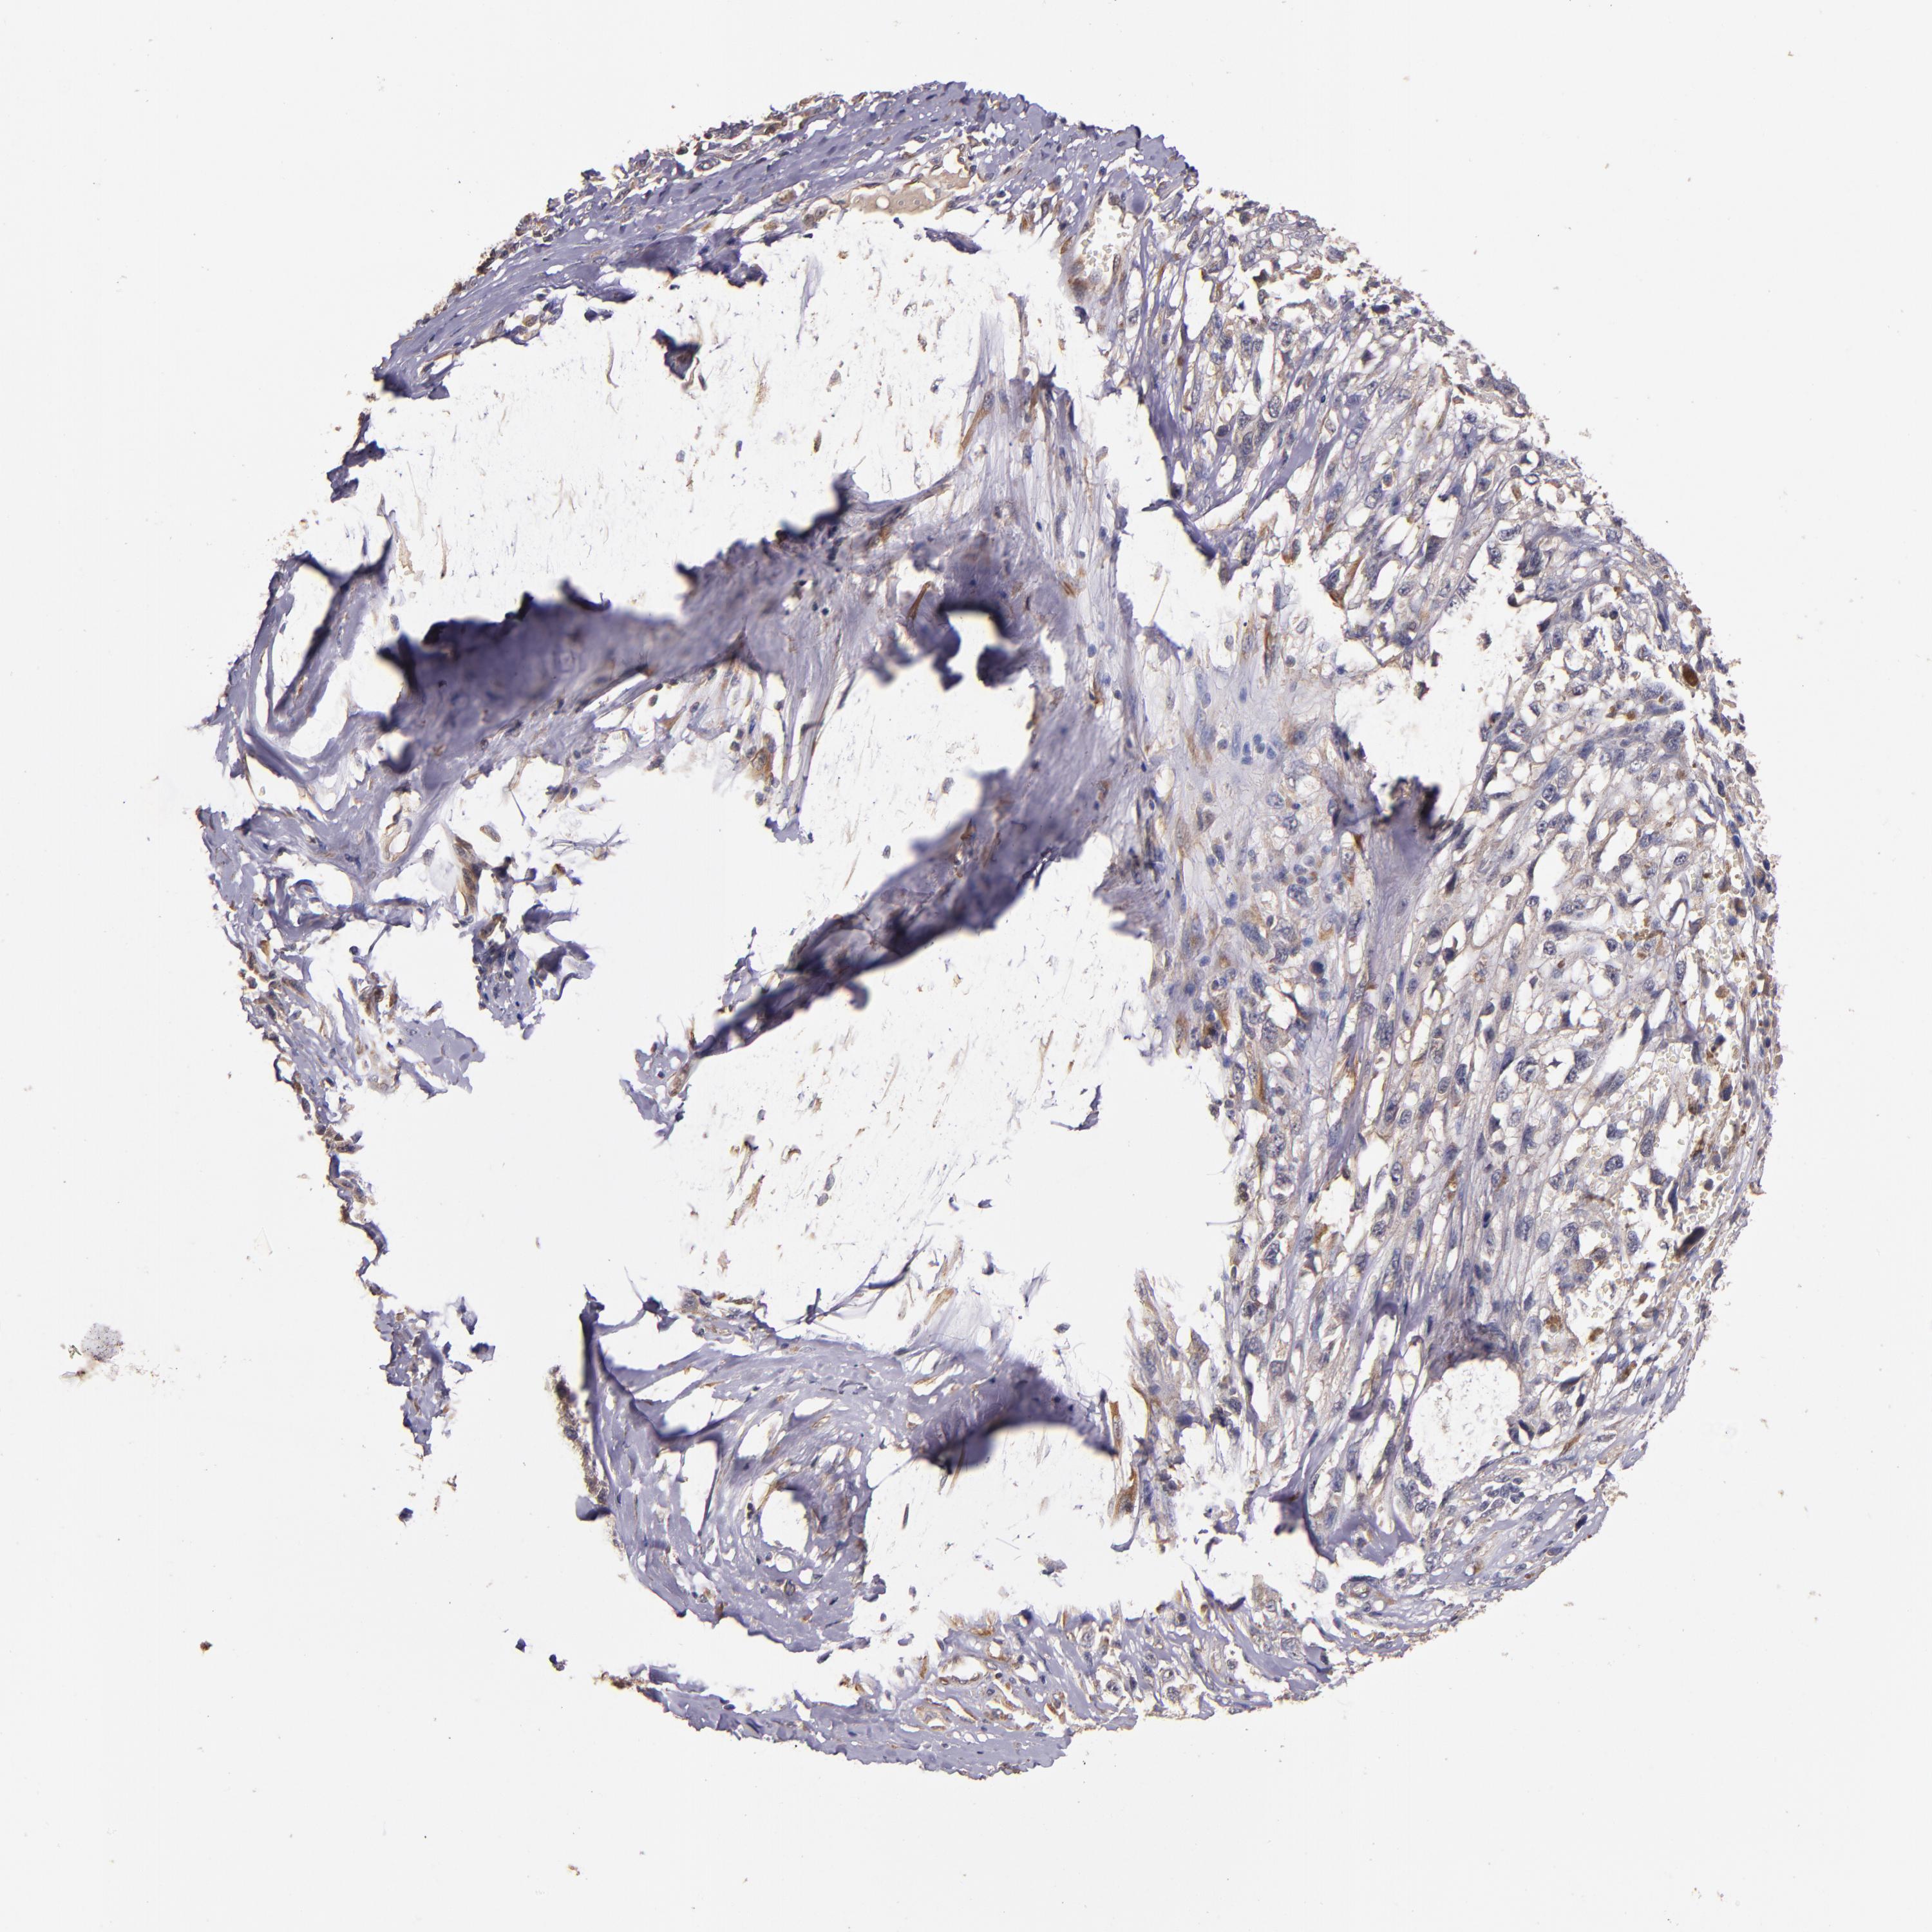

MELANOMA - Protein expressioni

A mouse-over function shows sample information and annotation data. Click on an image to view it in a full screen mode. Samples can be filtered based on level of antibody staining by selecting one or several of the following categories: high, medium, low and not detected. The assay and annotation is described here.

Note that samples used for immunohistochemistry by the Human Protein Atlas do not correspond to samples in the TCGA dataset.

Antibody stainingi

Antibody staining in the annotated cell types in the current human tissue is reported as not detected, low, medium, or high, based on conventional immunohistochemistry profiling in selected tissues. This score is based on the combination of the staining intensity and fraction of stained cells.

Each image is clickable and will lead to virtual microscopy that enables deeper exploration of all samples and also displays staining intensity scores, fraction scores and subcellular localization as well as patient and tissue information for each sample.

Antibody HPA002859

Antibody CAB011655

Staining

High

Medium

Low

Not detected

Intensity

Strong

Moderate

Weak

Negative

Quantity

>75%

75%-25%

<25%

None

Location

Nuclear

Cytoplasmic/membranous

Cytoplasmic/membranous,nuclear

Malignant melanoma, NOS

Malignant melanoma, Metastatic site